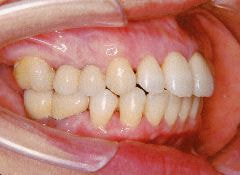

治療例2 (補綴処置+矯正)